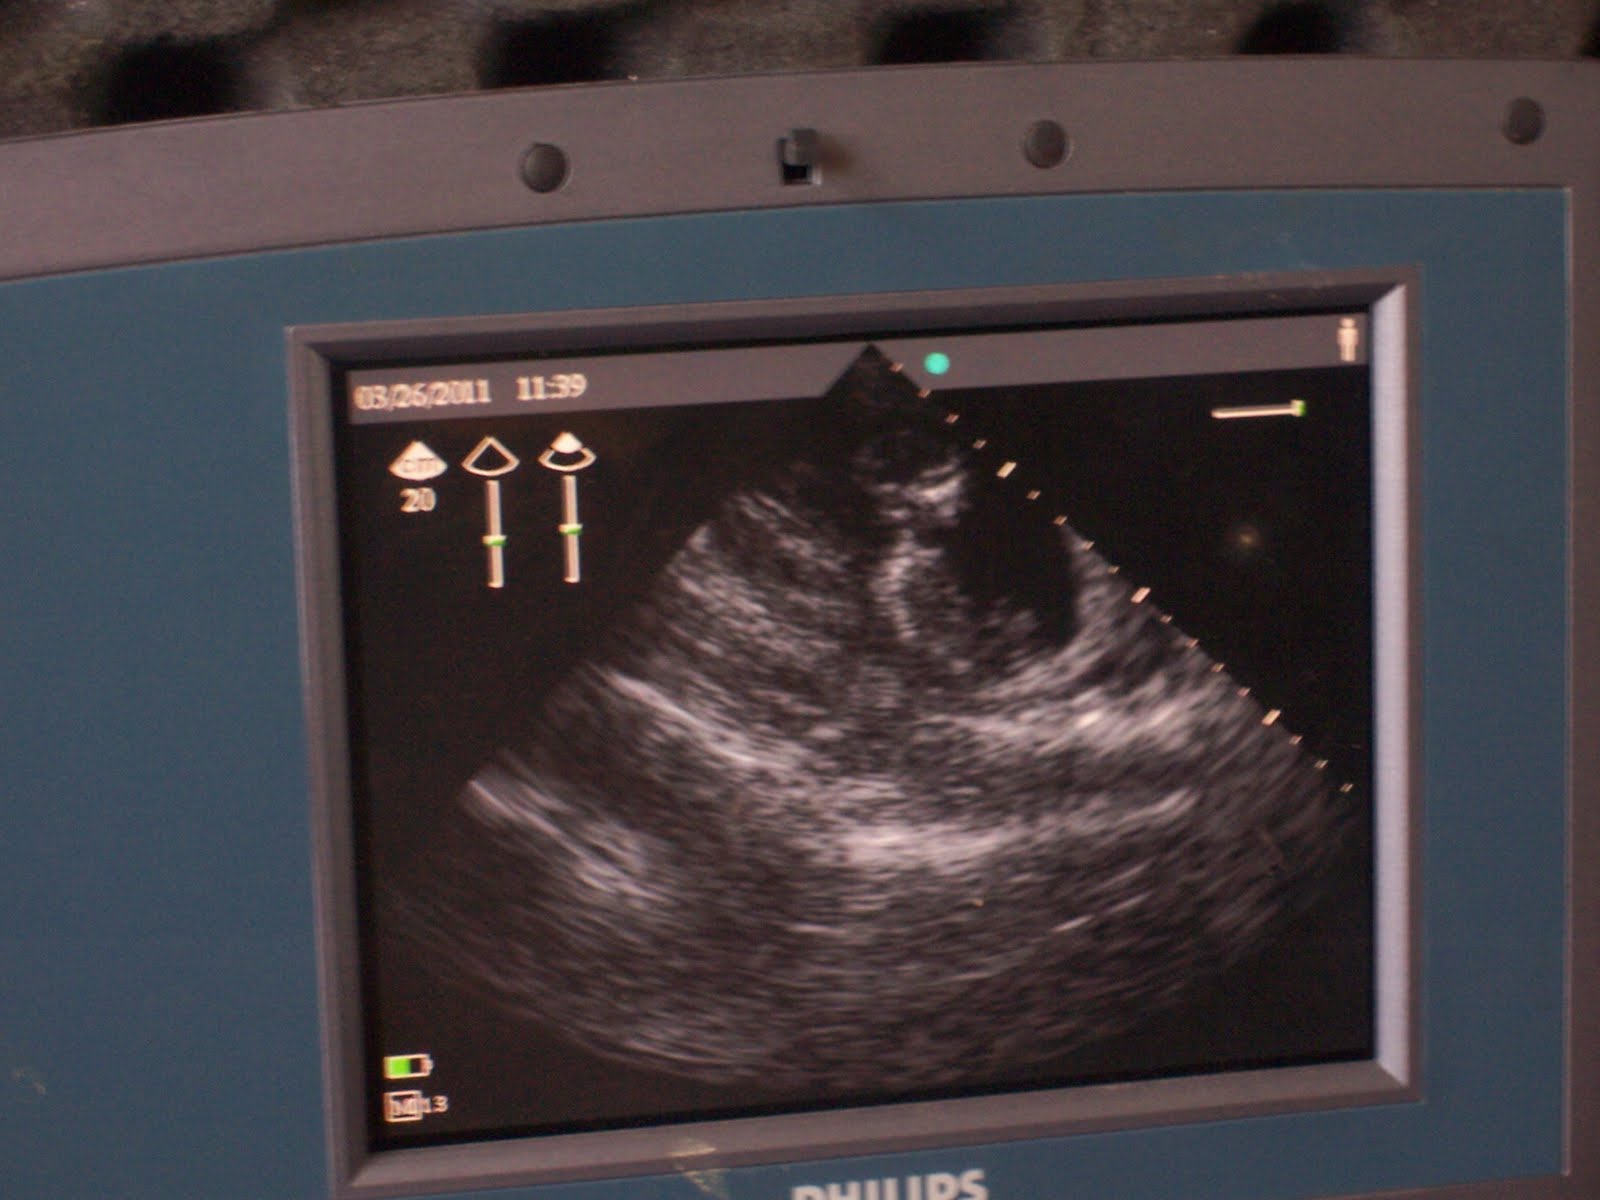

A lady who is 16weeks pregnant with twins but her placenta is in the wrong place and we are trying to keep the children and mom alive.

One of the twins from the lady in the first picture